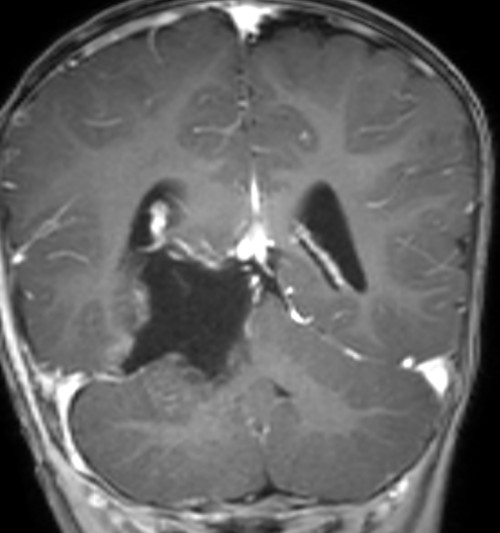

2026年3月3日,由张玉琪院长主刀,经枕下幕上入路小脑幕上、下病变切除术。手术历时4小时,镜下近全切除肿瘤,周围脑干、颅神经及血管保护良好,出血仅100ml。术后患儿转入NICU(新生儿重症监护病房),次日平稳返回普通病房。病理确诊为胚胎性肿瘤,WHO Ⅳ级(世界卫生组织(WHO)根据肿瘤恶性程度划分的最高级别(IV级)的恶性肿瘤)。术后虽康复情况充满挑战,但由医护团队通过中西医结合治疗后顺利恢复健康,并于术后第17天顺利启动第一周期化疗。

脑肿瘤术后1